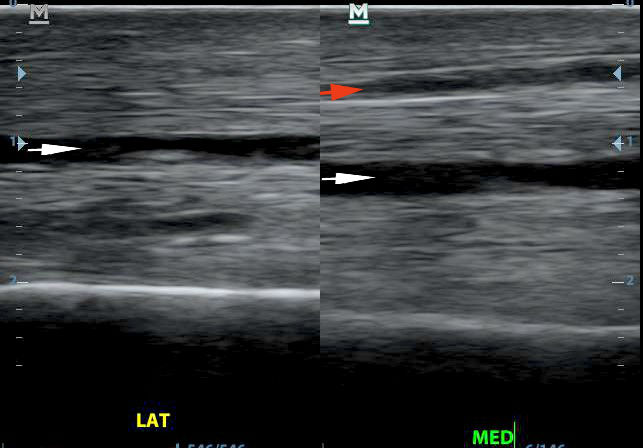

Ki látja az apró sérülést a bal oldali kép bal felső részében? A jobb oldalon az ín ép részlete.

Bal oldalon az ép, jobb oldalon a sérült ínszakasz hosszirányú felvétele. A piros nyíl a sérülést mutatja, itt a fehér, egyenes, erős rostok helyett feketés mező látható. A fehér nyilak az inak közötti rést mutatják. A kettő megkülönböztetése pontos anatómiai ismereteket igényel.